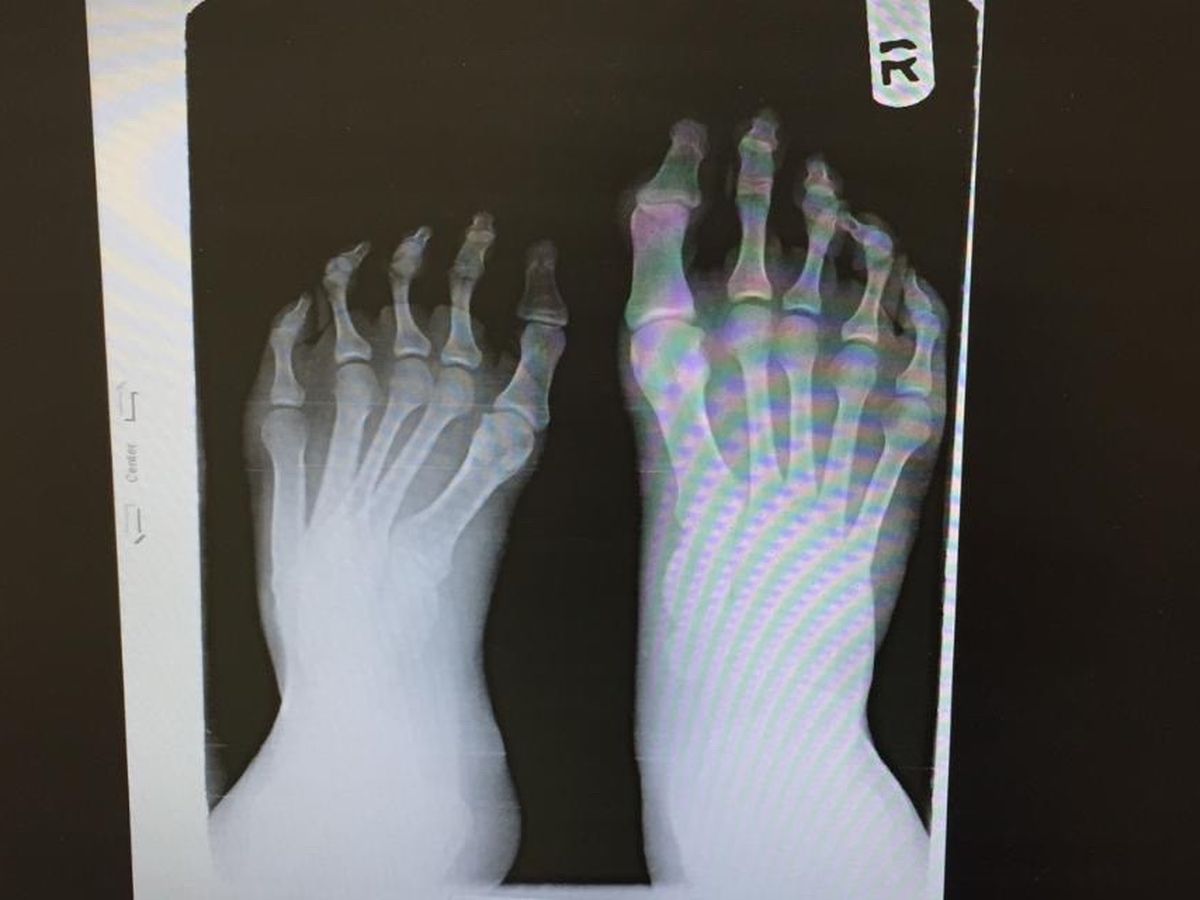

As many of you know, my brother Dj aka Derek has been battling with club foot since he was born. With unsuccessful reconstructive surgeries as a baby, his leg began to develop differently than the other. The pain and issues he had as a child stopped him from his love of playing football. He had to always buy shoes that fit one foot, but was 3 sizes too big for his club foot. After years of various braces, supports, stockings and on going struggles, he kept on going.

In 2014 he had his first complete reconstructive surgery. For months he wore an external fixator which every day needed to be turned to slowly reconstruct the bones in his foot, toes & ankle. He worked with his Dr for two years between physical therapy, readjustments, more braces, casts and special shoes. This surgery not only caused my brother to have a permanent limp, but now was in CONSTANT pain. He went from running, walking long periods of time and being a normal young 20 year old guy to one who cannot run, and walks with a struggle.

After this surgery and years of struggle... he was now worse off than before. This never stopped him.. he kept on working, he kept on fighting and he never let it get in the way of his happiness. After some time, Dj came in contact with a special team of Dr’s in NYC. Hoping to keep his foot, he went to this team and after months and months of appointments, pictures, preparation and OUT OF POCKET EXPENSES, he was ready for his SECOND reconstructive surgery! Although this one corrected a lot of the wrong doings from before, it never fixed the issue of pain and limping he now suffered from.